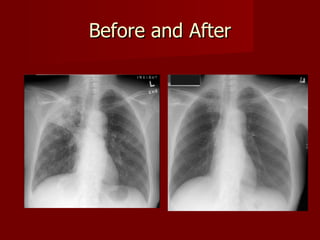

Diagnosed Skin test Chest X-rays Analysis of sputum

Before and After

Diagnosed Skin testChest X-rays Analysis of sputum

• #7 X-rays can reveal evidence of active tuberculosis pneumonia. Other times, the X-rays may show scarring (fibrosis) or hardening (calcification) in the lungs, suggesting that the TB is contained and inactive. They may also find legions/cavities in the upper part of the lung if there is active TB Skin test- a small amount of purified extract from dead tuberculosis bacteria is injected under the skin. If a person is not infected with TB, then no reaction will occur at the site of the injection (a negative skin test). If a person is infected with tuberculosis, however, a raised and reddened area will occur around the site of the test injection. If TB infection recent then false positive. Vaccine if take as a child, still possible to catch as an adult. Will give a false positive on skin Tb test so need x ray to confirm A positive TB skin test or TB blood test only tells that a person has been infected with TB bacteria.   It does not tell whether the person has  latent TB infection  (LTBI)   or has progressed to  TB disease .   If the body is able to form scar tissue (fibrosis) around the TB bacteria, then the infection is contained in an inactive state. Such an individual typically has no symptoms and cannot spread TB to other people. The scar tissue and lymph nodes may eventually harden, like stone, due to the process of calcification of the  scars  (deposition of calcium from the bloodstream in the scar tissue). These scars often appear on X-rays and imaging studies like round marbles and are referred to as a granuloma.